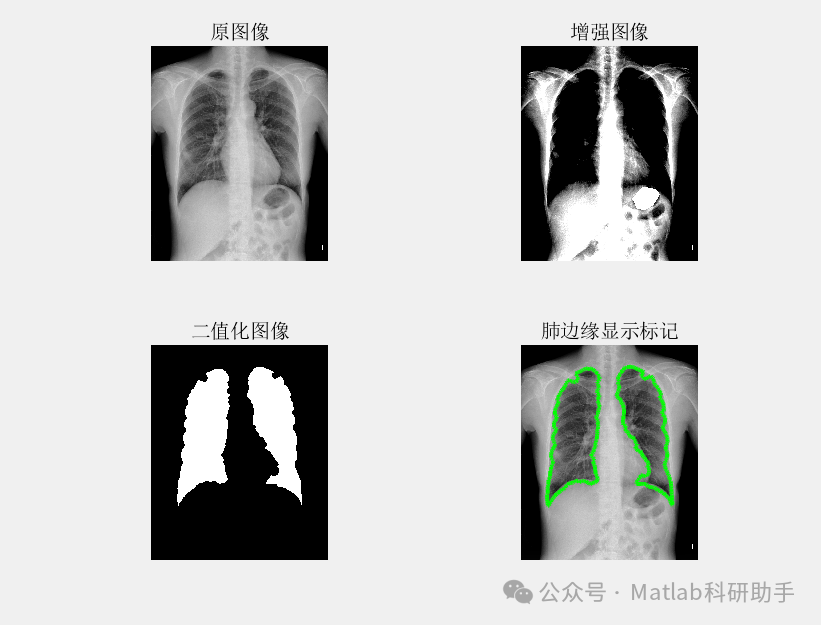

胸片分割作为计算机辅助诊断系统中的关键环节,旨在从胸片图像中精确提取肺部区域,为后续疾病诊断和定量分析提供基础。传统的胸片分割方法往往依赖于人工设计的特征或复杂的图像处理流程,鲁棒性较差。近年来,深度学习凭借其强大的特征学习能力,为胸片分割带来了新的突破。

基于最小误差法的胸片分割系统,通常采用深度学习模型,如U-Net或其变体,作为核心分割引擎。该模型通过大量标注数据进行训练,学习从胸片图像到肺部区域掩膜的映射关系。其核心思想是最小化模型预测的分割结果与真实标注之间的误差,从而实现准确的分割。

具体的训练过程中,常用的损失函数包括Dice Loss和Binary Cross Entropy Loss等。Dice Loss关注分割区域的重叠度,更适用于解决类别不平衡问题。Binary Cross Entropy Loss则逐像素地比较预测概率和真实标签,适用于像素级别的分割任务。通过选择合适的损失函数并优化模型参数,能够有效降低分割误差,提高分割精度。

⛳️ 运行结果